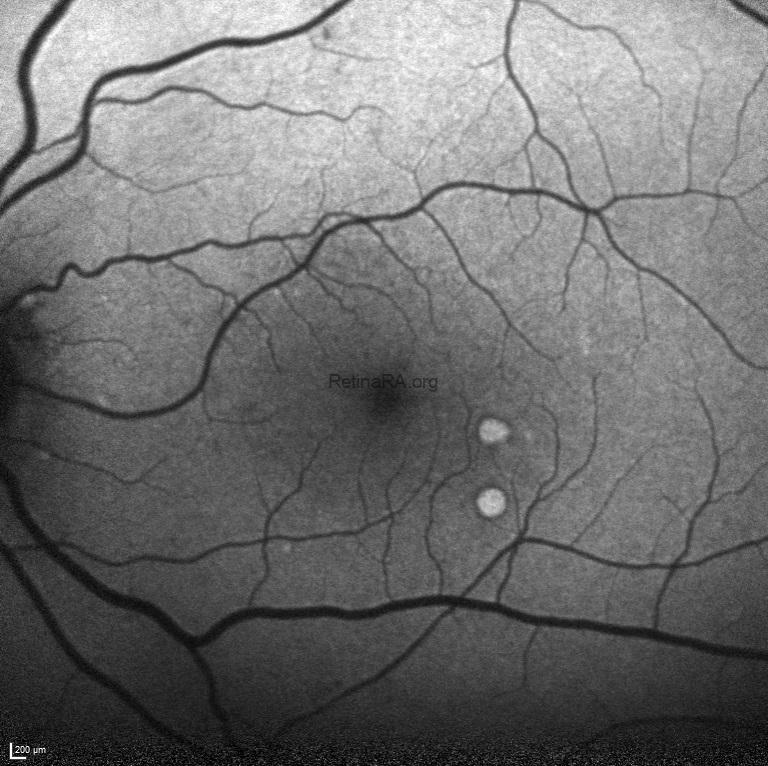

Fundus autofluorescence imaging exhibited the hyper-autofluorescence of drusen and hypo-autoflurescence of retinal microaneurysms and hemorrhages.